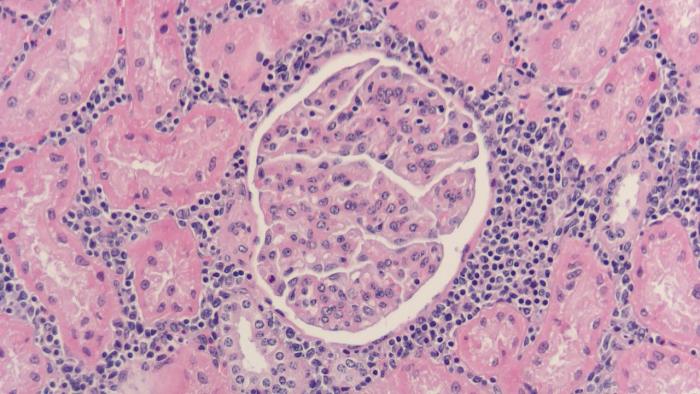

3病理検査

筋肉や臓器の組織学的な検査も行い,異常を判定しています。